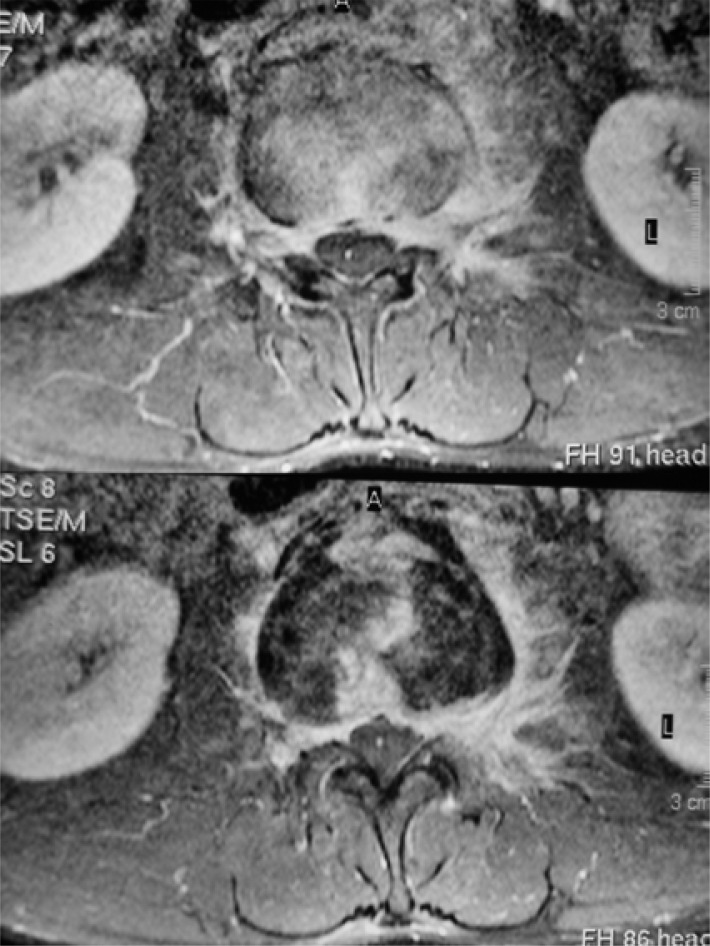

Brucellosis is a zoonotic disease caused by Gram-negative bacteria of the Brucella genus that can be acquired through contact with a contaminated animal or its secretions. The course of the disease can be acute, chronic, or persistent. Axial skeleton and central nervous system (CNS) are among the most common affected locations and may be involved in each of the forms. Due to the varying clinical picture of the disease, diagnosis is made mainly on the basis of laboratory examinations that detect specific IgM and IgG antibodies in blood or other biological material and/or cultures. Imaging methods, especially magnetic resonance imaging, can aid in establishing proper diagnosis, monitoring of the disease and, to some extent, enable differential diagnosis before obtaining the laboratory tests results. The aim of this review is to present imaging features of Brucella infection of the spine and CNS and provide the recent advancements in the field.

Abstract Image